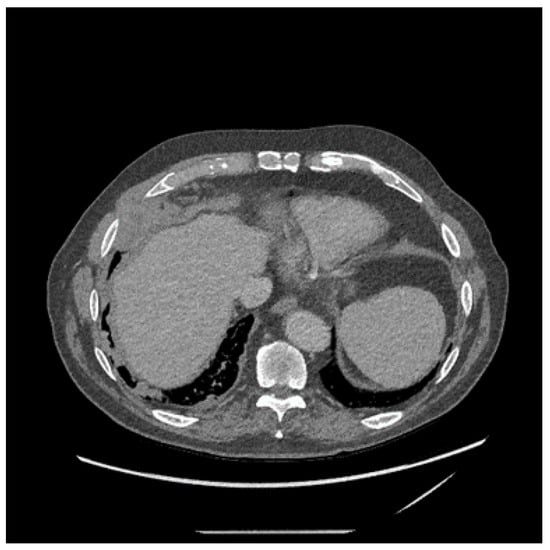

- Yildirim, H.; Metintas, M.; Entok, E.; Ak, G.; Ak, I.; Dundar, E.; Erginel, S. Clinical value of fluorodeoxyglucose-positron emission tomography/computed tomography in differentiation of malignant mesothelioma from asbestos-related benign pleural disease: An observational pilot study. J. Thorac. Oncol. 2009, 4, 1480–1484. [Google Scholar] [CrossRef]

- Kruse, M.; Sherry, S.J.; Paidpally, V.; Mercier, G.; Subramaniam, R.M. FDG PET/CT in the management of primary pleural tumors and pleural metastases. AJR Am. J. Roentgenol. 2013, 201, W215–W226. [Google Scholar] [CrossRef]